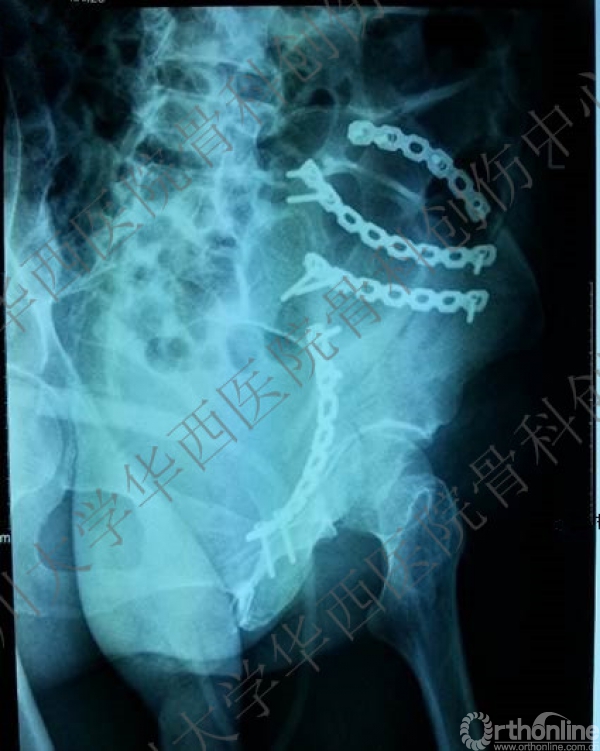

诊断:左髋臼双柱骨折。

入院后行左股骨髁上牵引,积极术前准备,做CT,证实双柱骨折的诊断。

术后X线片

这是术后的X线片,患侧正位、髂骨斜位、闭孔斜位。